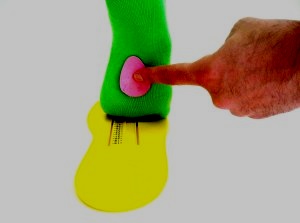

Mai mult, sub stiva transversal a arcadelor longitudinale ale unei benzi de cauciuc este plasată, se adaugă picătură metatarsian, care este instalat direct sub capetele metatarsiene în prezența flatfoot cruce.

Cum este modelarea suport plantar? Foarte simplu: cu ajutorul unei benzi de cauciuc trăgând arcul longitudinal al ascensorului picior la înălțimea fiziologic și amprenta meniurile metatarsian formează arc transversal a piciorului. Manipularea dureaza 1 minut. Identic pentru a oferi o simulare a branțului pentru piciorul opus.